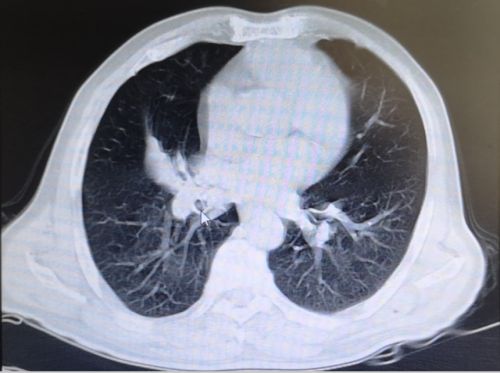

6月上旬,湖南宁乡75岁的姜爷爷连续4天发高烧,最高体温达到40.1℃,可自行退烧,除阵发性腹痛外没有其他不适。无规律的高热让平时身体硬朗的老人没了精气神,吃了几天中药不见好转,在家人的反复劝说下,来到湖南省人民医院就诊。初步筛查排除新冠肺炎后,老年医学中心何翠娥副主任医师仔细询问病史,并为其进行详细的体格检查, CT 检查提示:1.右下肺阻塞性肺炎;2.右下肺团块灶,性质待定,考虑肿瘤可能性大。随即将其收入老年医学中心二病室,做进一步的检查和治疗。